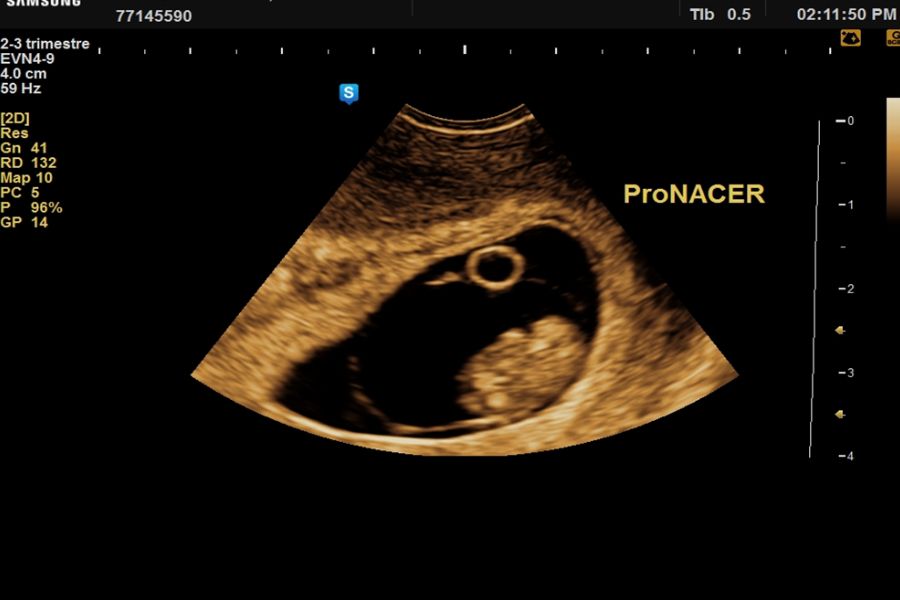

El momento óptimo para realizar el estudio ecográfico para cronicidad y animosidad es el 1er trimestre a partir de la semana 7, 11 a 14 con una sensibilidad > 98%, con una precisión menor pero aceptable en el segundo trimestre temprano (sensibilidad 90%).

Una membrana entre gemelos con el signo “Lambda “indica gemelos dicorionicos. El signo lambda se refiere a la proyección triangular del tejido que se extiende entre las capas de la membrana entremezclada desde una placenta dicorionica fusionada. Se observa mejor a las 10 a 14 semanas, se vuelve menos prominente después de las 20 semanas de gestación y puede desaparecer.